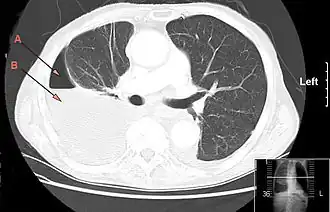

![]() Компьютерная томография, демонстрирующая массивный правосторонний гидропневмоторакс, обусловленный эмпиемой плевры. Стрелка A: газ, B: жидкость | |

Для хронической эмпиемы характерно формирование симптома барабанных палочек. Отмечается укорочение перкуторного звука и ослабление везикулярного дыхания с поражённой стороны. Для диагностики используется подсчёт лейкограммы, рентгенография и компьютерная томография грудной клетки, ультразвуковое исследование[2].